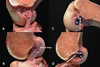

ACI overview: technique: benefits: limitatins ## Footnote ACI for patellar chondral defect

* cell therapy with goal of forming autologous "hyaline-like" cartilage *technique: arthroscopic harvest of cartilage from a lesser weight bearing area in the lab, chondrocytes are released from matrix and are expanded in culture defect is prepared, and chondrocytes are then injected under a periosteal patch sewn over the defect during a second surgery benefits may provide better histologic tissue than marrow stimulation long term results comparable to microfracture in most series include regeneration of autologous tissue, can address larger defects * benefits may provide better histologic tissue than marrow stimulation long term results comparable to microfracture in most series include regeneration of autologous tissue, can address larger defects * limitations must have full-thickness cartilage margins around the defect open surgery 2-stage procedure prolonged protection necessary to allow for maturation